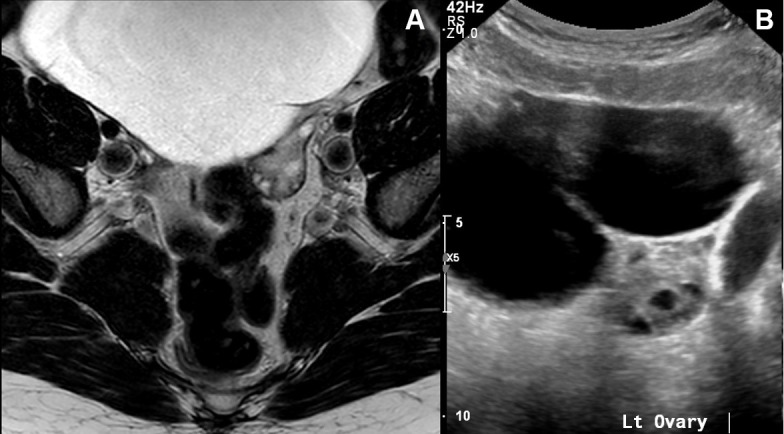

Figure 2.

(A) MRI pelvis demonstrating the cystic mass as independent structures from both ovaries. (B) Ultrasound pelvis showing the cystic lesion to be separated from the left multifollicular ovary.

She was seen by the gynaecologist who organised an MRI of the pelvis. Interestingly, the MRI pelvis did not depict the cyst to be arising from the ovaries (figure 2A). She was then referred to the general surgical clinic for further assessment. On clinical examination, her abdomen was distended but soft. The upper border of the cystic lesion was palpable at the epigastric region and non-tender.

Tumour markers including carcinoembryonic antigen, CA-19.9, CA-125 and chromogranin were all negative. A repeat pelvic USS was also inconclusive (figure 2B).